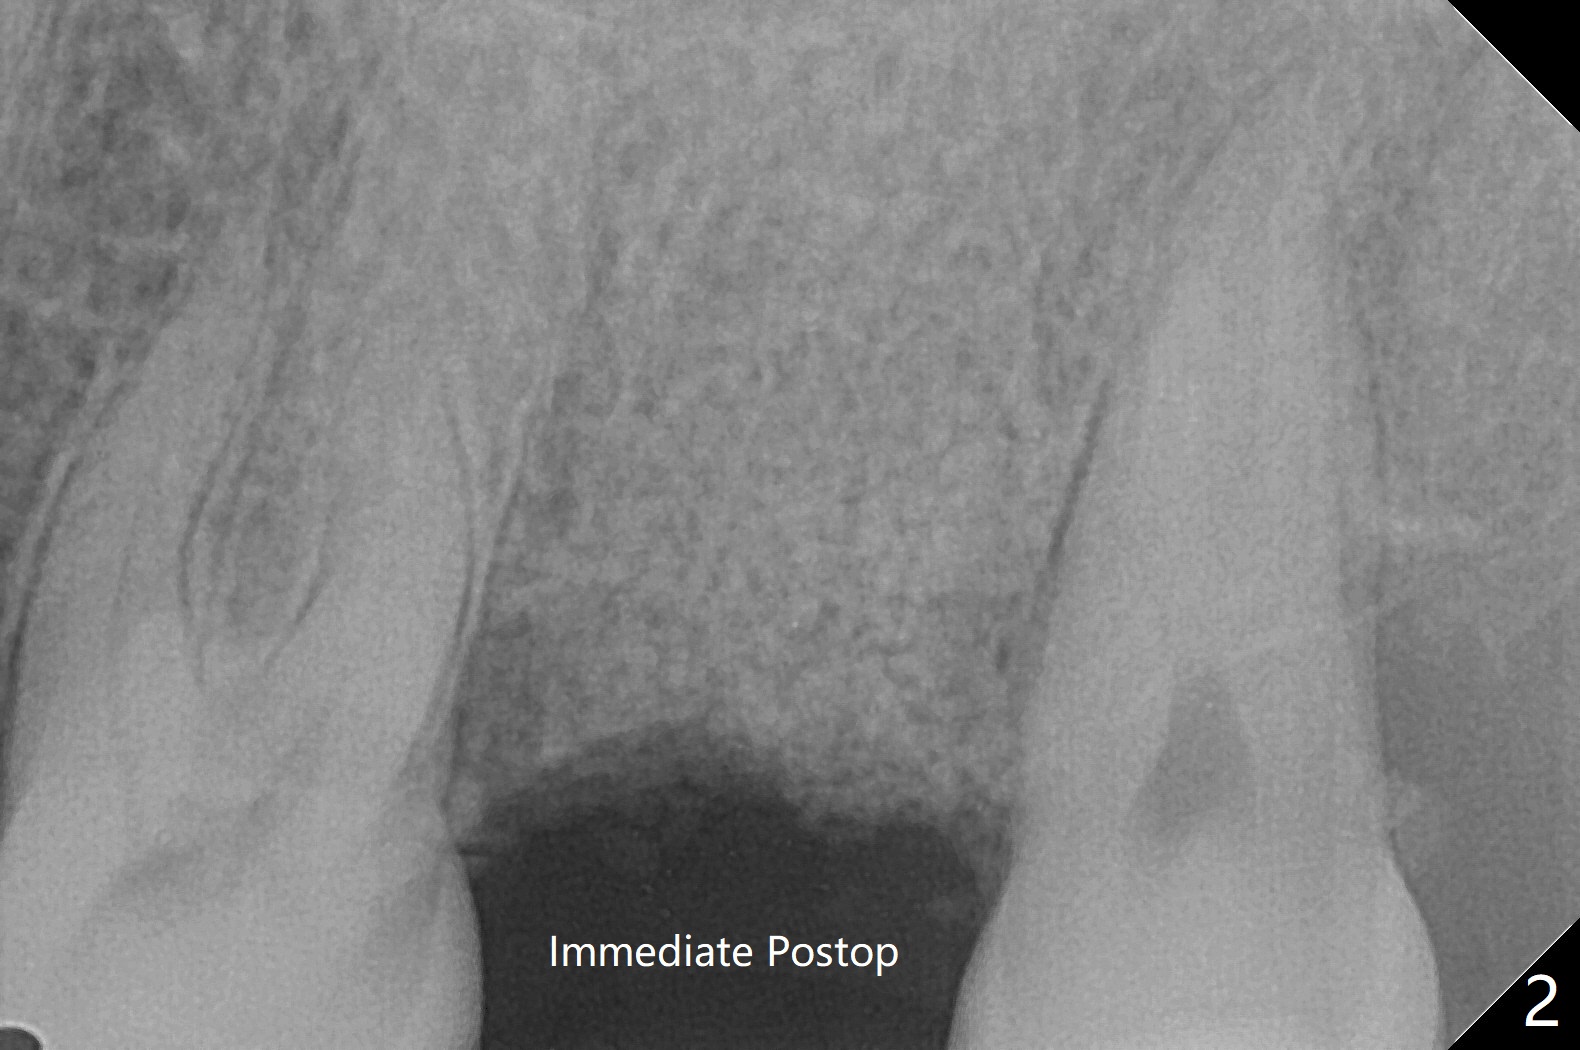

61岁女,胃病,不愿意保留左上7(图一),其实拔牙困难,牙齿小,牙钳显得大,无法旋转,摇把,最后不得不切断,分根拔除,没有肉芽组织或者骨板缺损。由于星期六病人多,使用GEM21S(~.25cc)与皮质骨(图二),Teflon,牙周胶水,牙周敷料固定骨粉。